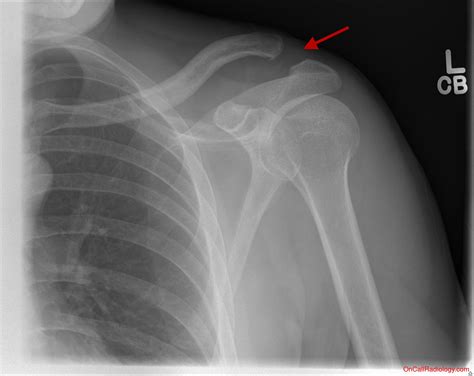

To grasp what happens during an Ac Tendon Injury, it helps to visualize where the injury occurs. The acromioclavicular joint is located at the top of the shoulder where the clavicle (collarbone) meets the acromion (a projection of the shoulder blade). These two bones are held together by a complex set of ligaments, specifically the AC ligaments and the coracoclavicular (CC) ligaments.

When you suffer an injury here, it is technically a ligamentous sprain or tear, but it is frequently categorized alongside tendon issues because of the stress placed on the surrounding musculature. Force applied to the shoulder, such as a direct blow or landing on an outstretched arm, can stretch or tear these stabilizing structures, leading to varying degrees of joint separation.

• A visible deformity or bump on top of the shoulder where the collarbone protrudes.